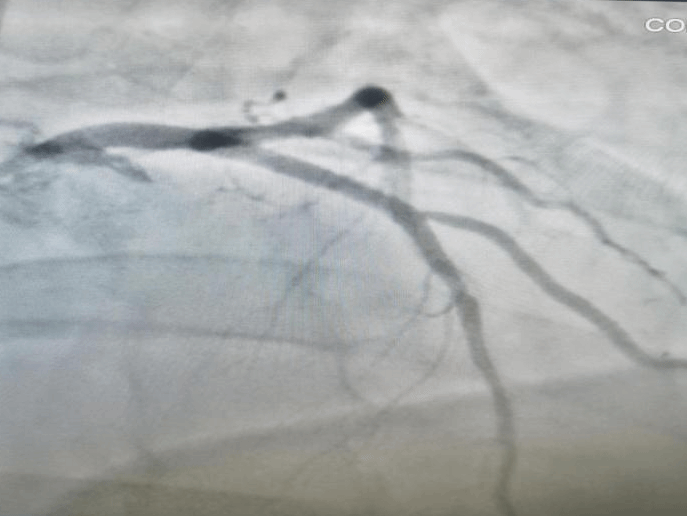

冠状动脉造影证实,患者心脏最重要的血管“前降支”闭塞,在前期准备充分的情况下,从患者转运入院到前降支血管打通,团队仅用时15分钟,为患者赢得了宝贵的“心肌存活时间”。